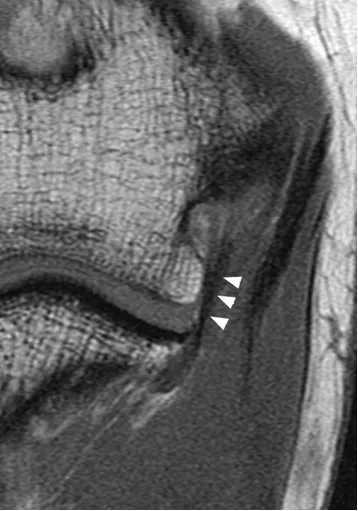

滑膜皱襞

后外侧滑膜皱襞,是关节滑膜增生折叠形成的结构,过度增生或损伤时可能引发关节不适。

(a)33 岁女性受试者的矢状位 T2 加权磁共振成像,以及(b)对应的示意图,清晰显示出后外侧滑膜皱襞的前后径(白色箭头所示)与头尾径(黑色箭头所示)。图中 AM 代表肘肌。

(c)与图 a 相同的磁共振影像,以及(d)对应的示意图,显示出肱骨小头的假性缺损(箭头所示),及其与后外侧滑膜皱襞的密切关联。图中 AM 代表肘肌。